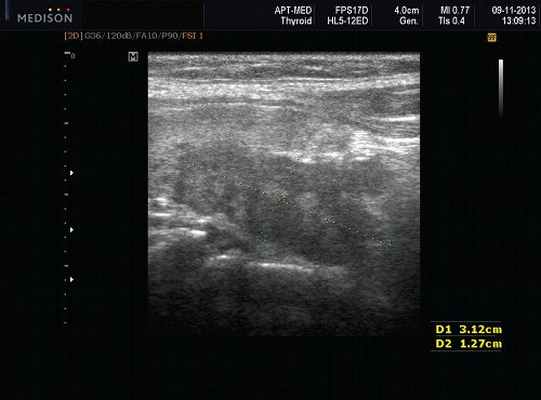

- обструктивные сиаладениты, развивающиеся при затруднении оттока слюны при обструкции выводного протока камнем (рис. 5-7) или сгустившимся секретом, а также вследствие рубцового стеноза протока. По распространенности процесса различают очаговый, диффузный сиаладениты и сиалодохит - воспаление выводного протока. Течение процесса может быть острым и хроническим;

Рис. 5. Камень протока поднижнечелюстной слюнной железы.

Рис. 6. Камень в паренхиме поднижнечелюстной слюнной железы.

Рис. 7. Камень в протоке поднижнечелюстной слюнной железы.